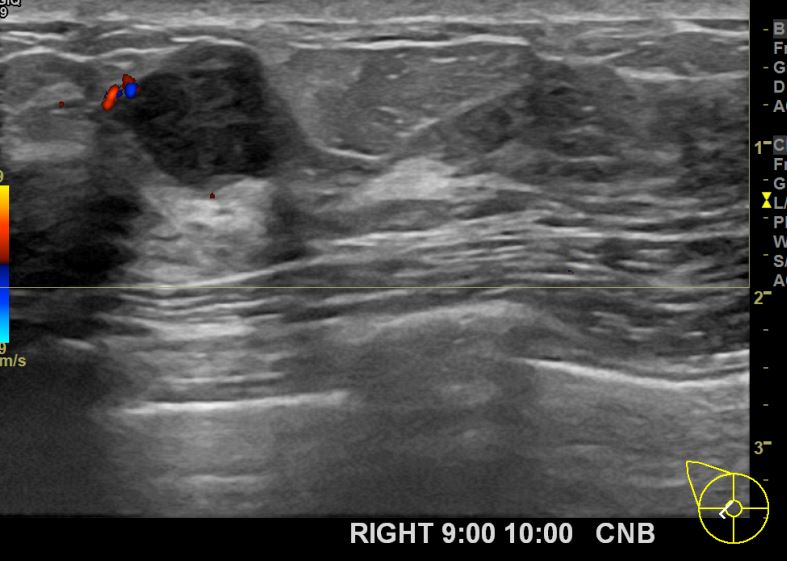

아산유외과개원후 674번째 유방암진단

상기환자 외부검사상 이상소견으로 내원하신 40대여성으로 우측에 의심스러운혹 조직검사시행해 유방암 진단되었습니다.